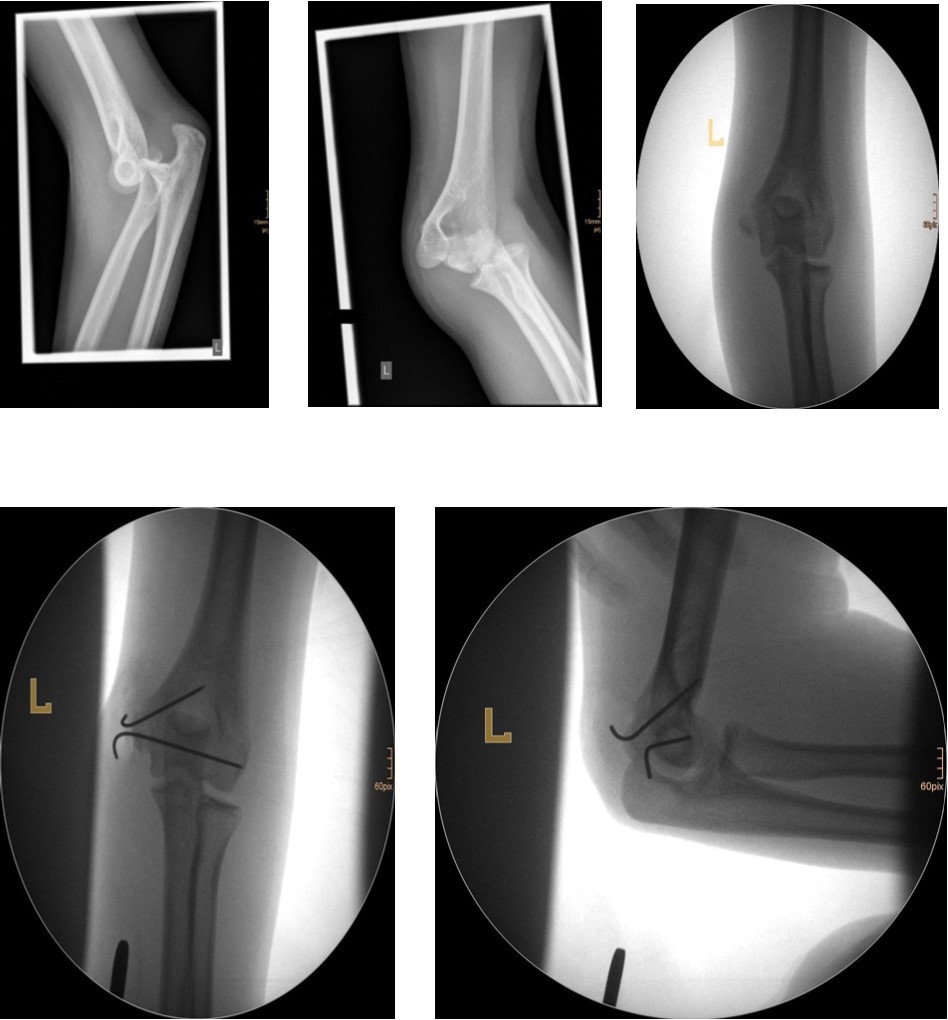

Treatment

Undisplaced fractures are simply immobilized in a cast or posterior splint. As with fractures of the lateral condylar physis union may be slow. In fractures treated promptly, results have been satisfactory. Because there is usually more displacement in older children, the results in this age group are not as satisfactory as those in younger children, who tend to have relatively nondisplaced fractures. For displaced fractures, open reduction with internal fixation is the most often used treatment method.

The fracture fragment can be approached by a posteromedial incision that allows good exposure of both the fracture site and the ulnar nerve. Fixation is easily achieved with smooth K-wires or with screws in older adolescents. Two wires are necessary because of the sagittal rotation forces exerted on the fracture fragment by the common flexor muscles. Figure 4 and Figure 5.

Figure 4.14 year old female patient with a elbow dislocation and a dislocated left epicondyle fracture which was treated by open reduction and osteosynthesis with two divergent Kirschner wires (personal collection)

Figure 5.9 year old female patient with a elbow dislocation and a dislocated right medial condyle fracture which was treated by open reduction and osteosynthesis with a screw (personal collection)